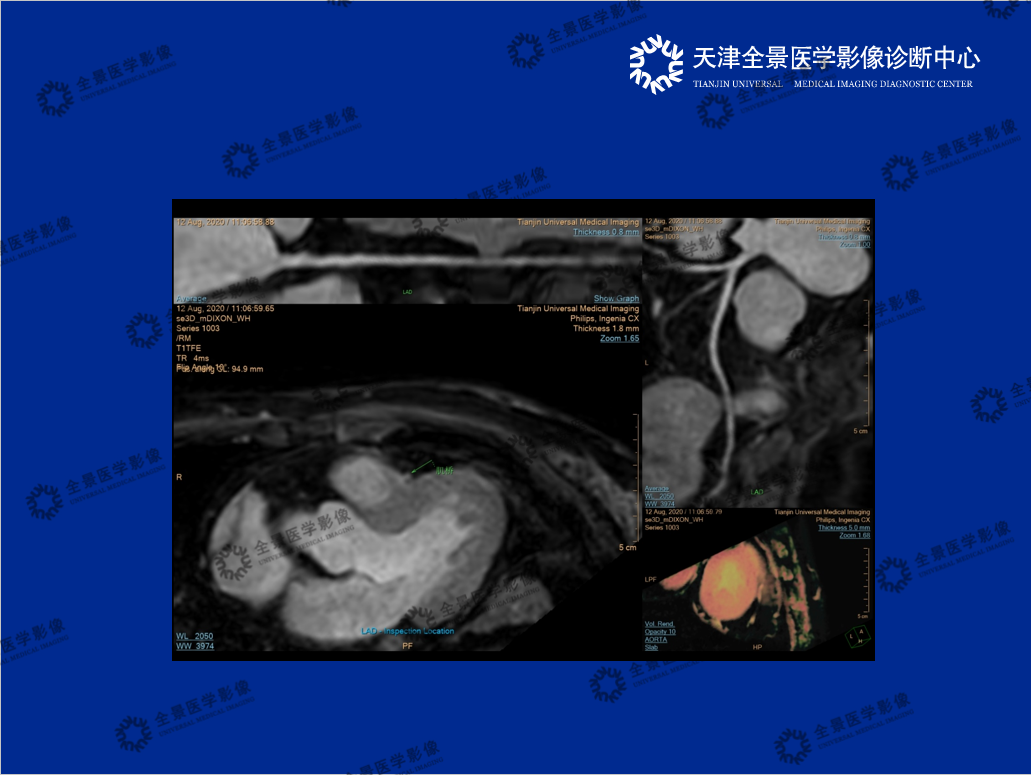

介绍了心脏磁共振的检查原理,分享了丰富案例,总结了CMRA的优势,即无创、避免碘对比剂过敏、无辐射,特别是弥补了冠脉严重钙化,CTA无法评估管腔狭窄程度的局限性。

2.《3.0T磁共振冠状动脉成像》 汇报人:宫健

详细介绍了无对比剂心脏磁共振(CMR)与对比剂心脏磁共振(CMRA)的成像对比,展现了任意层面成像的优势。